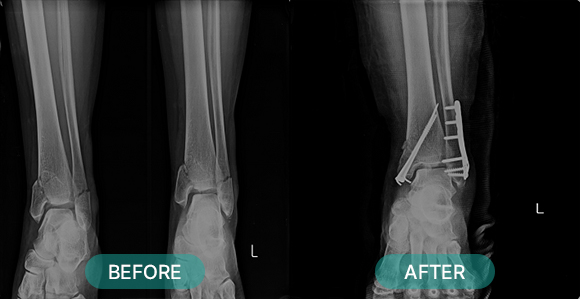

관혈적 정복이란 골절된 부위를 절개하고 뼈를 노출시켜 눈으로 직접 보면서 골절편을 정확하게 맞추는 방법으로 금속판과 나사 고정법, 핀고정법, 나사고정법, 골수 내정 고정법, 인공 관절 치환술, 외고정 기구 고정법 등등 여러 방식이 있습니다.

부위별 골절치료